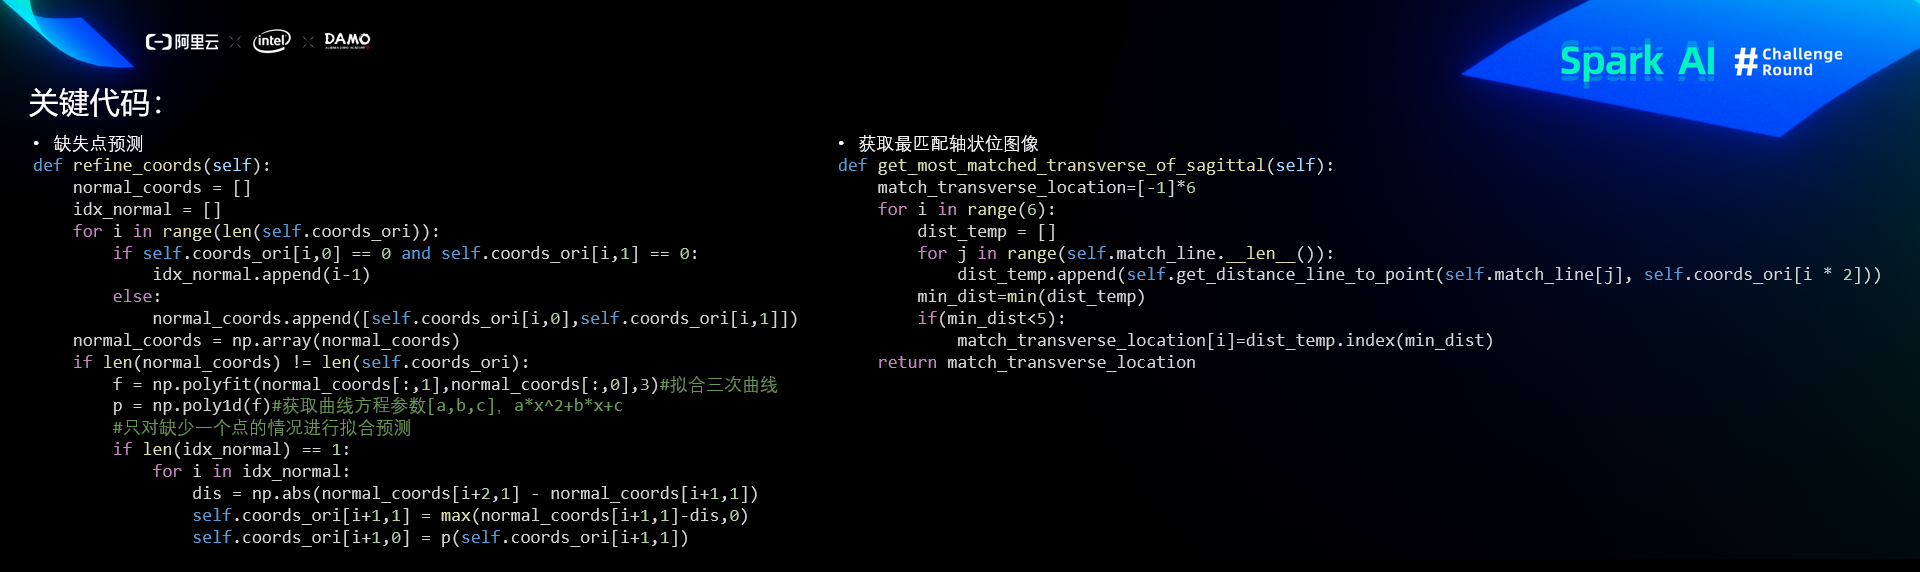

关键代码